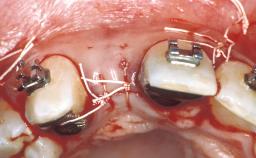

In October 1999, the 35-year-old female patient, a nonsmoker, presented at our clinic with a persisting deciduous canine 63 that displayed all the clinical signs and symptoms of an ankylosed primary tooth, including inadequate crown volume, discoloration, locally perturbed occlusal plane, inharmonious course of the associated soft tissue, advanced root resorption, and increased mobility. The patient had a strong wish for a durable improvement of the situation with a clear emphasis on dental/gingival esthetics. The patient was in good general health, and her medical history revealed no significant findings.